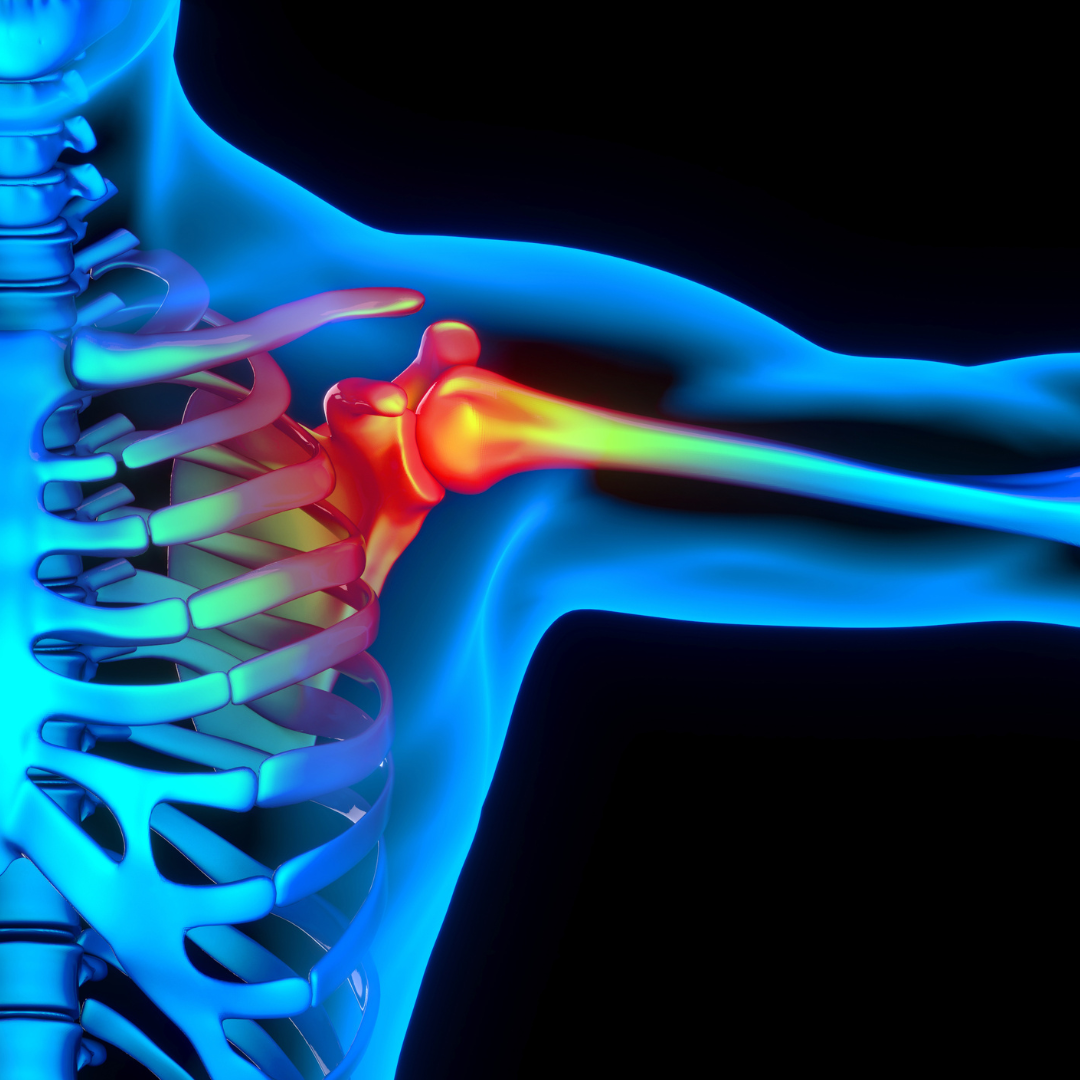

Utesnitveni sindrom rame

Kaj morate vedeti?

Utesnitveni sindrom rame nastane zaradi stiskanja kit rotatorne manšete in burze med kostnimi strukturami. To povzroči vnetje in bolečino, še posebej pri dvigovanju roke nad glavo. Najpogosteje se pojavi pri športnikih in ljudeh, ki pogosto izvajajo ponavljajoče se gibe nad višino ramen.

• Bolečina pri dviganju roke ali pri gibanju nad glavo

• Oslabitev mišic ramenskega obroča

• Občutek pokanja ali trenja pri premikanju roke

• Nočna bolečina, ki otežuje spanje na prizadeti strani

• Postopno zmanjševanje gibljivosti in moči rame

Zdravljenje:

Fizikalna terapija s specifičnimi vajami za krepitev rotatorne manšete in izboljšanje gibljivosti zmanjša simptome. Protivnetna zdravila pomagajo pri lajšanju bolečin in vnetja. V hujših primerih se uporablja terapija z udarnimi valovi ali kortikosteroidne injekcije. Če konzervativno zdravljenje ni uspešno, se lahko izvede operativni poseg za sprostitev prostora pod akromionom. Po operaciji sledi večmesečna rehabilitacija.

Preventivni ukrepi

Pravilna tehnika gibanja in krepitev mišic rotatorne manšete zmanjšujeta tveganje za utesnitveni sindrom. Ogrevanje pred vadbo in postopno stopnjevanje intenzivnosti preprečujeta poškodbe. Izogibanje ponavljajočim se gibom nad glavo zmanjšuje preobremenitve ramenskega sklepa.